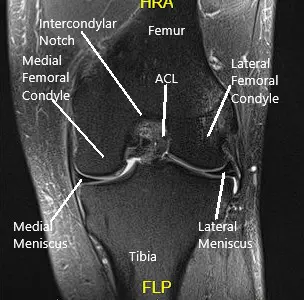

MRI examination of the left knee suggested a complex tear of the posterior horn of the medial meniscus. Small horizontal cleavage tear of the body of the lateral meniscus.Moderate joint effusion with synovitis.

MRI of the knee in the sagittal and coronal section.